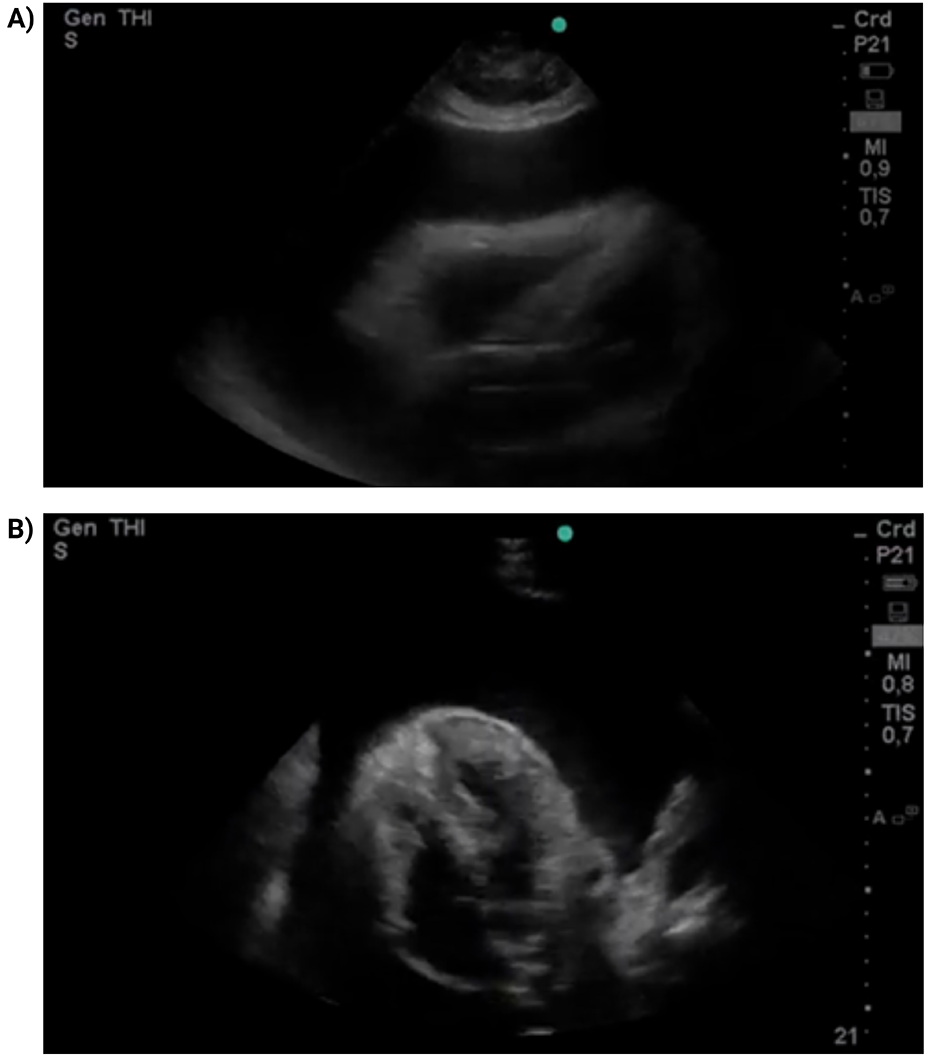

Given the clinical suspicion of cardiac tamponade, focused cardiac ultrasound (FoCUS) was performed in the resuscitation area using a portable Mindray Z5 ultrasound system with a phased-array transducer. The examination was conducted at the bedside by an emergency physician trained in point-of-care ultrasonography. It showed a massive circumferential pericardial effusion measuring approximately 28 mm in diastole, with right atrial systolic and right ventricular diastolic collapse, consistent with tamponade physiology (Figure 1; Supplementary Videos S1–S2). Interventional cardiology was urgently consulted, and emergency pericardiocentesis was performed via a subxiphoid approach. A total of 1,200 mL of serous fluid was drained, and a Hemovac catheter was left in situ for 24 h. The patient experienced immediate relief of dyspnea following the procedure.

FoCUS parasternal long-axis view (A) and subxiphoid four-chamber view (B) A massive circumferential pericardial effusion is observed (28 mm in diastole), with collapse of right-sided chambers.